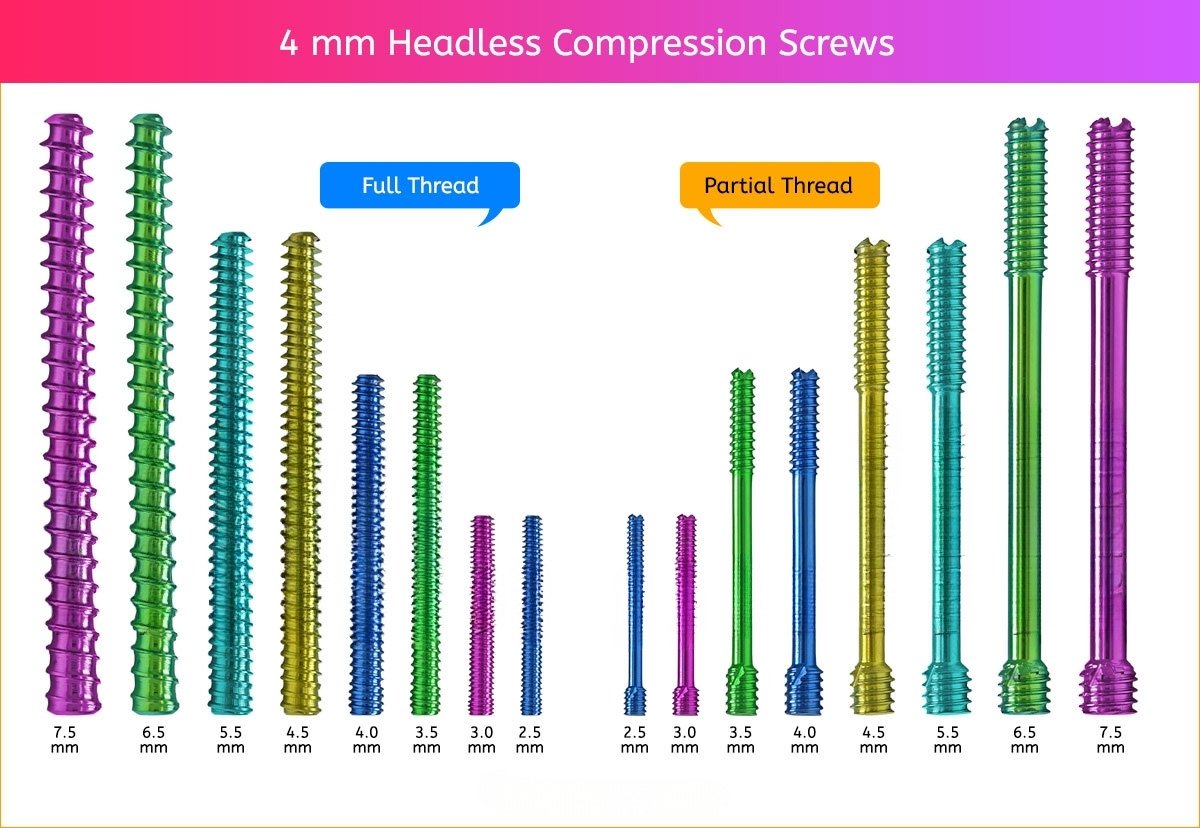

4 mm Headless Compression Screw

4 mm Screws Length

8mm, 10mm, 12mm, 14mm, 16mm, 18mm, 20mm, 22mm, 24mm, 26mm, 28mm, 30mm, 32mm, 34mm, 36mm, 38mm, 40mm, 42mm, 44mm, 46mm, 48mm, 50mm, 55mm, 60mm, 65mm, 70mm, 75mm and 80mm.